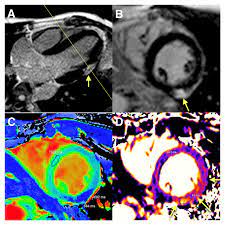

Suspected Subclinical Myocarditis Detected By Cardiac Magnetic Resonance Imaging Late Post Covid 19 Recovery Journal Of Cardiology Cases

Suspected Subclinical Myocarditis Detected By Cardiac Magnetic Resonance Imaging Late Post Covid 19 Recovery Journal Of Cardiology Cases from els-jbs-prod-cdn.jbs.elsevierhealth.com